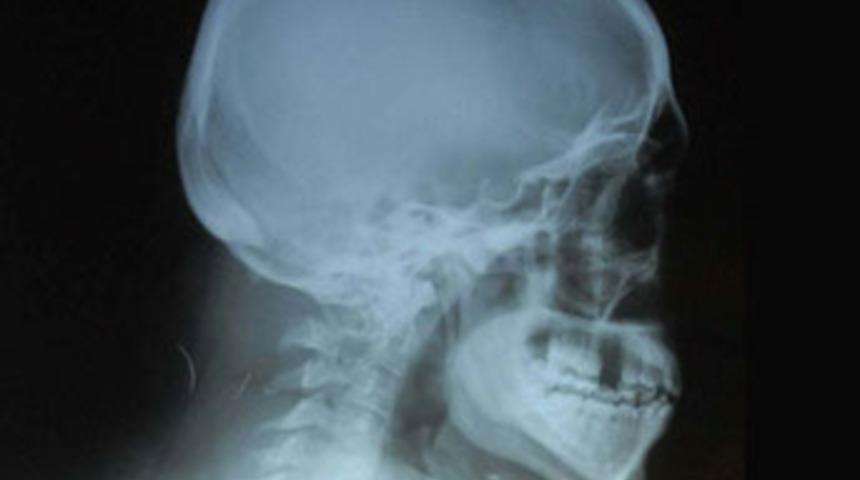

Buna rağmen acıları dinmeyen Aktaş, özel bir sağlık merkezine gidip beyin tomografisi çektirdi. Aktaş’ın ensesine yakın yerde metal uçlu, cisimler saptandı. Durumdan şüphelenen Aktaş’ın gittiği Alsancak Devlet Hastanesi’nde çektirdiği röntgen filmlerinde, ensesinde iki iğne ucunun unutulduğu anlaşıldı. Bunun üzerine Aktaş, operasyonu gerçekleştiren 4 doktorun cezalandırılması için İzmir Bölge İdare Mahkemesi’ne başvurdu.